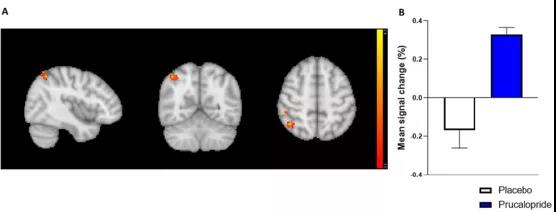

眾所周知,很多精神疾病常常伴隨著認(rèn)知功能障礙,認(rèn)知障礙不僅局限于記憶缺陷,還包括學(xué)習(xí)、注意力、語(yǔ)言以及處理速度等方面的障礙。這類(lèi)障礙會(huì)對(duì)生活質(zhì)量產(chǎn)生相當(dāng)大的負(fù)面影響,所以迫切需要開(kāi)發(fā)可以改善與精神疾病相關(guān)的認(rèn)知缺陷的治療方法。